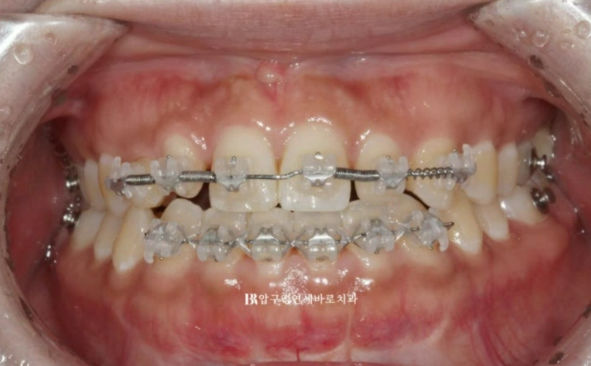

얕은 교합을 깊게 만들기 위해서는 스스로 고무줄을 걸 수 있는 클리피씨 장치가 효과적입니다.

23.05

치료 시작 4개월째 교정이 거의 완성된 모습입니다.

유치를 교정 치료 계획에 포함시킬때 가장 중요한 원칙은 유치는 함부로 움직이면 안된다입니다.

유치 특성상 교정력에 잘 반응하지도 않고 엄하게 치근흡수만 일어납니다.

좌우 라미네이트 두께와 사이즈가 밸런스 있게 제작이 되도록 공간 분배가 끝났고